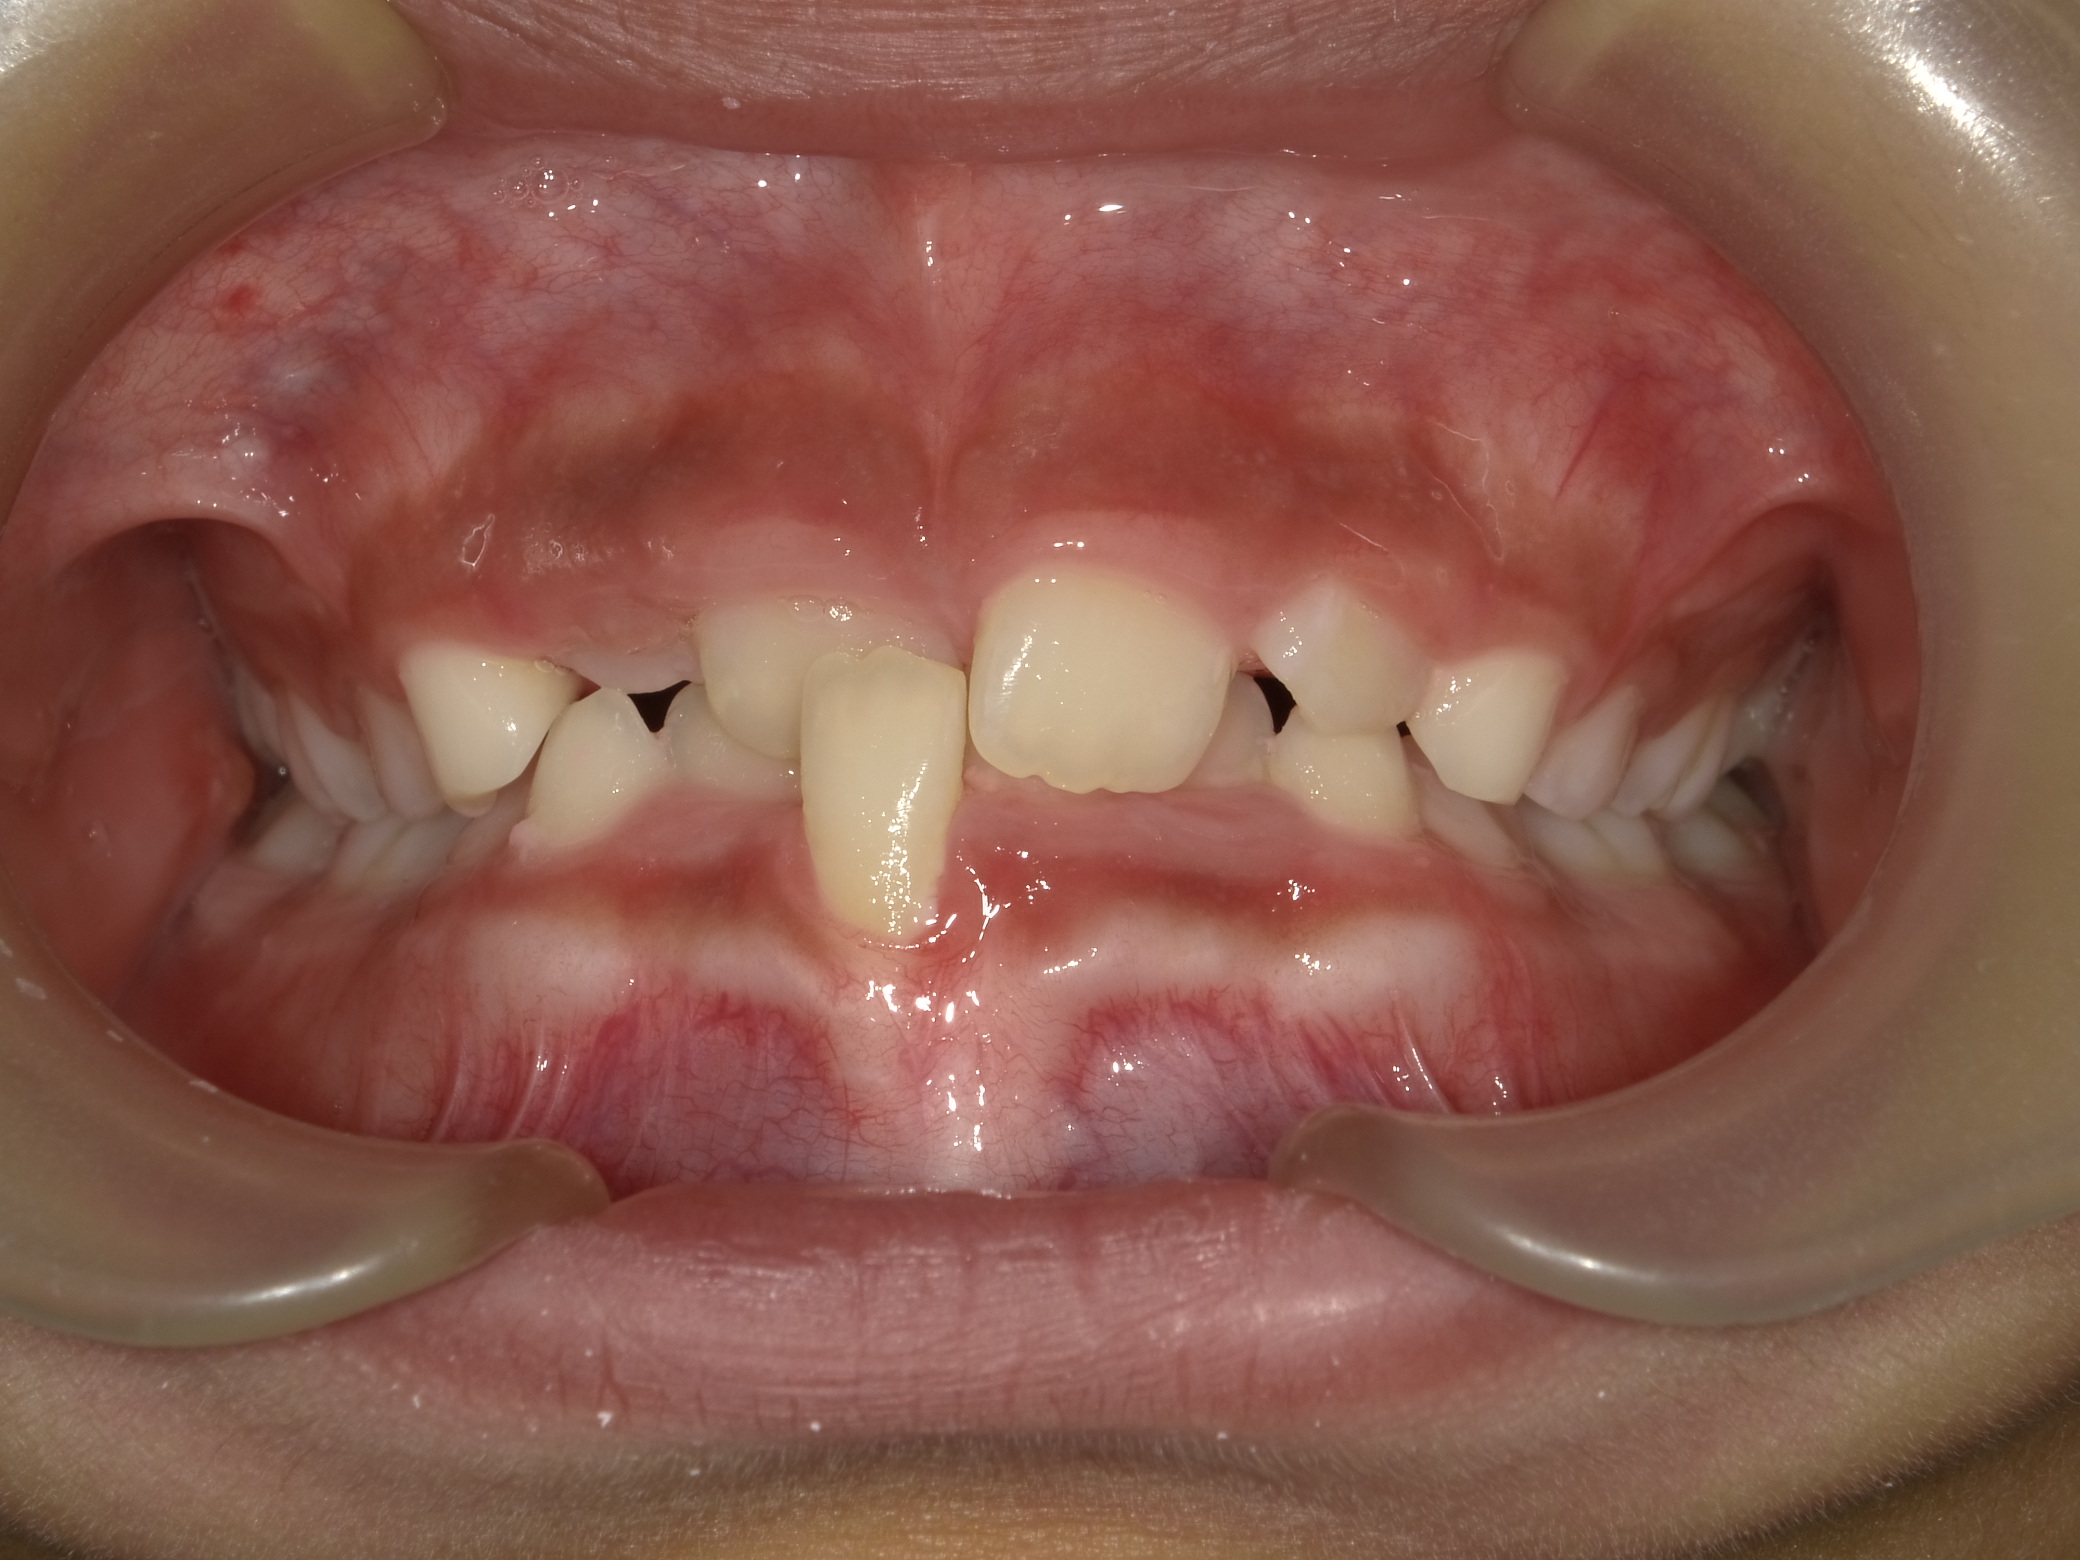

| 症例分類 | 交叉咬合 |

|---|---|

| 主訴 | 前歯がずれて咬んでいる |

| 年齢 | 9歳5ヶ月 |

| 性別 | 女性 |

| 抜歯部位 | なし |

| 使用装置 | 拡大装置、上顎前歯部のセクショナルアーチ装置、取り外し式保定装置 |

| 治療期間 | 1年2ヶ月 |

| 費用 | 相談料0円、検査料50,000円 動的矯正治療費330,000円 調整料6600円×15回分 保定装置料0円 |

| リスク・注意点 | 個々の歯の大きさに対して顎が小さく、歯が並ぶスペースが不足したために交叉咬合が生じています。これらを改善するために、幅の狭搾している歯列を側方に拡大した後、前歯を排列しました。

歯の動き方には個人差があり、予想された治療期間が延長する可能性があります。 治療中は矯正歯科装置が歯の表面に付いており、歯が磨きにくくなるため、むし歯や歯周病が生じるリスクが高まります。ハミガキを適切に行ってお口の中を常に清潔に保ち、さらに、かかりつけ歯科医に定期的に受診することが大切です。 矯正歯科装置の使用状況、定期的な通院など、矯正歯科治療には患者さんの協力が必要であり、それらが治療結果や治療期間に影響します。 治療の経過によっては当初予定していた治療計画を変更する可能性があります。 保定装置の装着時間が十分確保できない場合、歯並びや、咬み合せの「後戻り」が生じる可能性があります。 上下両側第二大臼歯の萌出を観察する必要があります。 |